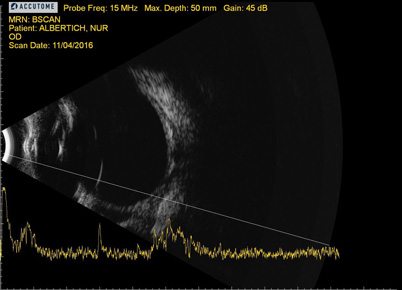

Se realizó una ecografía para descartar otras patologías en el segmento posterior.